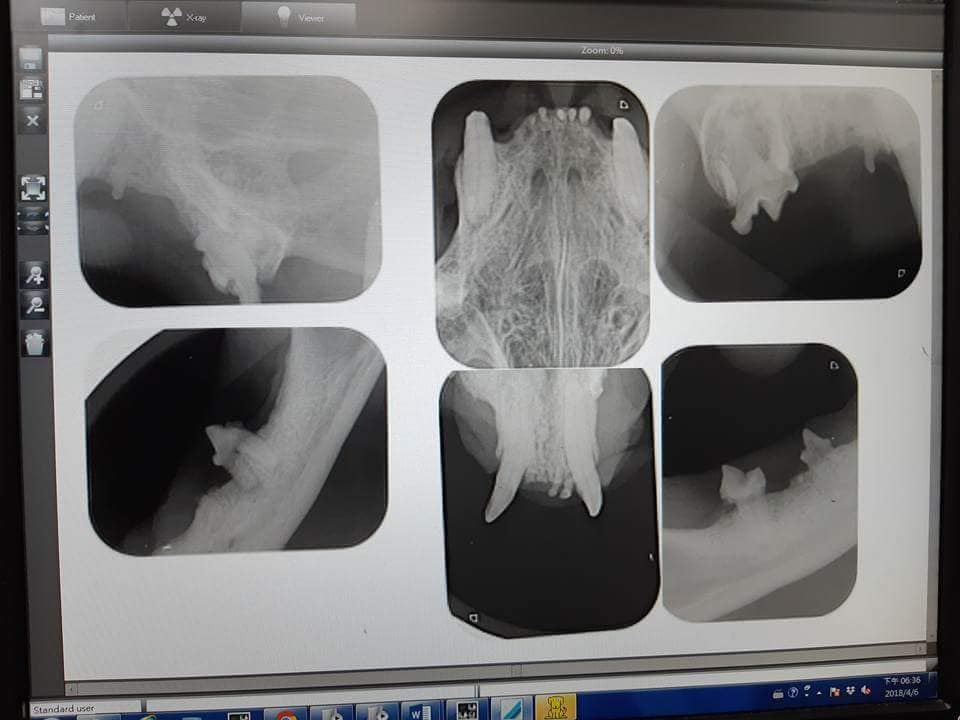

主題: 嚴重結石拔牙的帥帥 申請者姓名: 臺北市支持流浪貓絕育計劃協會 花色: 申請日期: 2018-05-09 15:28:20 申請者部落格: 申請者臉書網址: http://admin.tnrtw.org/hospice_add.php 所在縣市/合作醫院: 台北市/沐恩動物醫院 治療費用: 12400元 需求人數: 26人 已結案 (2024-06-01 13:12:38) 報名人員: 小P(已付款)、Naommi(已付款)、幸 x2(已付款)、陳昱先 x2(已付款)、Szumin Yu(已付款)、凜雪夜(已付款)、Ya-Jyun Huang(已付款)、Kristy Lee x2(已付款)、麥克 x15(已付款)、 候補人員: 動物病情說明: 帥帥的牙齒結石很嚴重,下排有一顆牙齒從外觀就可以明顯的看出來應該是會疼痛,

也就是齒冠吸收病,砝郎質跟牙齦接觸的部份被破壞時,牙結石就會貼上,而導致牙髓外露,牙齒就容易有疼痛感,因此就會有流口水的現象,

照X光檢視牙根狀況後醫生認為要拔牙,牠的血檢報告,紅白血球,血小板都正常,免疫球蛋白有稍為高了一些,是因為牙齒正在發炎,指數並沒有超出太多,都在正常的標準內,最主要是肝腎指數不能太差,才可以接受麻醉,於是便在4/6進行拔牙手術,一共拔了6顆牙。